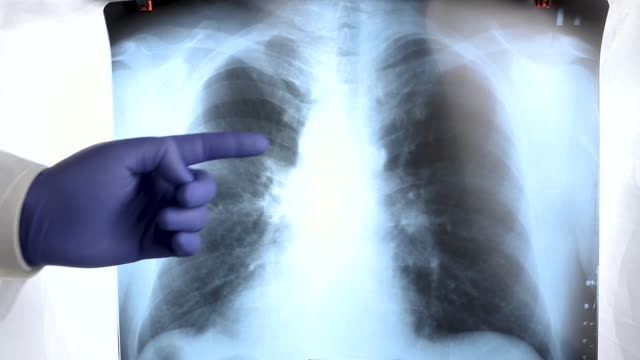

폐암은 유병률과 사망률이 높은 암 종 중 하나로, 조기 발견과 예방이 매우 중요합니다. 아직까지 폐암의 정확한 원인을 모두 파악하지 못했지만, 흡연을 포함한 흡연 관련 요인을 피하는 것이 폐암 예방에 큰 도움이 될 것입니다.

또한, 정기적인 건강 검진, 특히 엑스레이 등의 폐 검사를 받는 것도 중요합니다. 호흡기 증상이나 다른 이상 증상이 있을 경우, 빨리 의료 전문가와 상담하여 필요한 검사를 받는 것이 생명을 지킬 수 있는 선택일 수 있습니다.

폐암은 매우 위험한 질병이지만, 조기 발견과 예방을 위한 노력을 통해 그 위험을 줄일 수 있습니다. 건강한 생활 습관과 정기적인 검진은 폐암을 포함한 다양한 질병으로부터 우리를 보호하는 데 중요한 역할을 합니다.